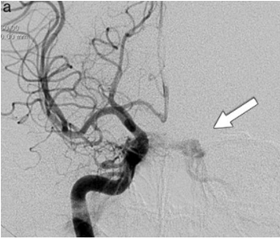

• Angiografía cerebral

Angiografía cerebral

Egas publicó el primer trabajo oficial sobre angiografía cerebral luego de realizar múltiples estudios con los diversos tipos de contrastes.